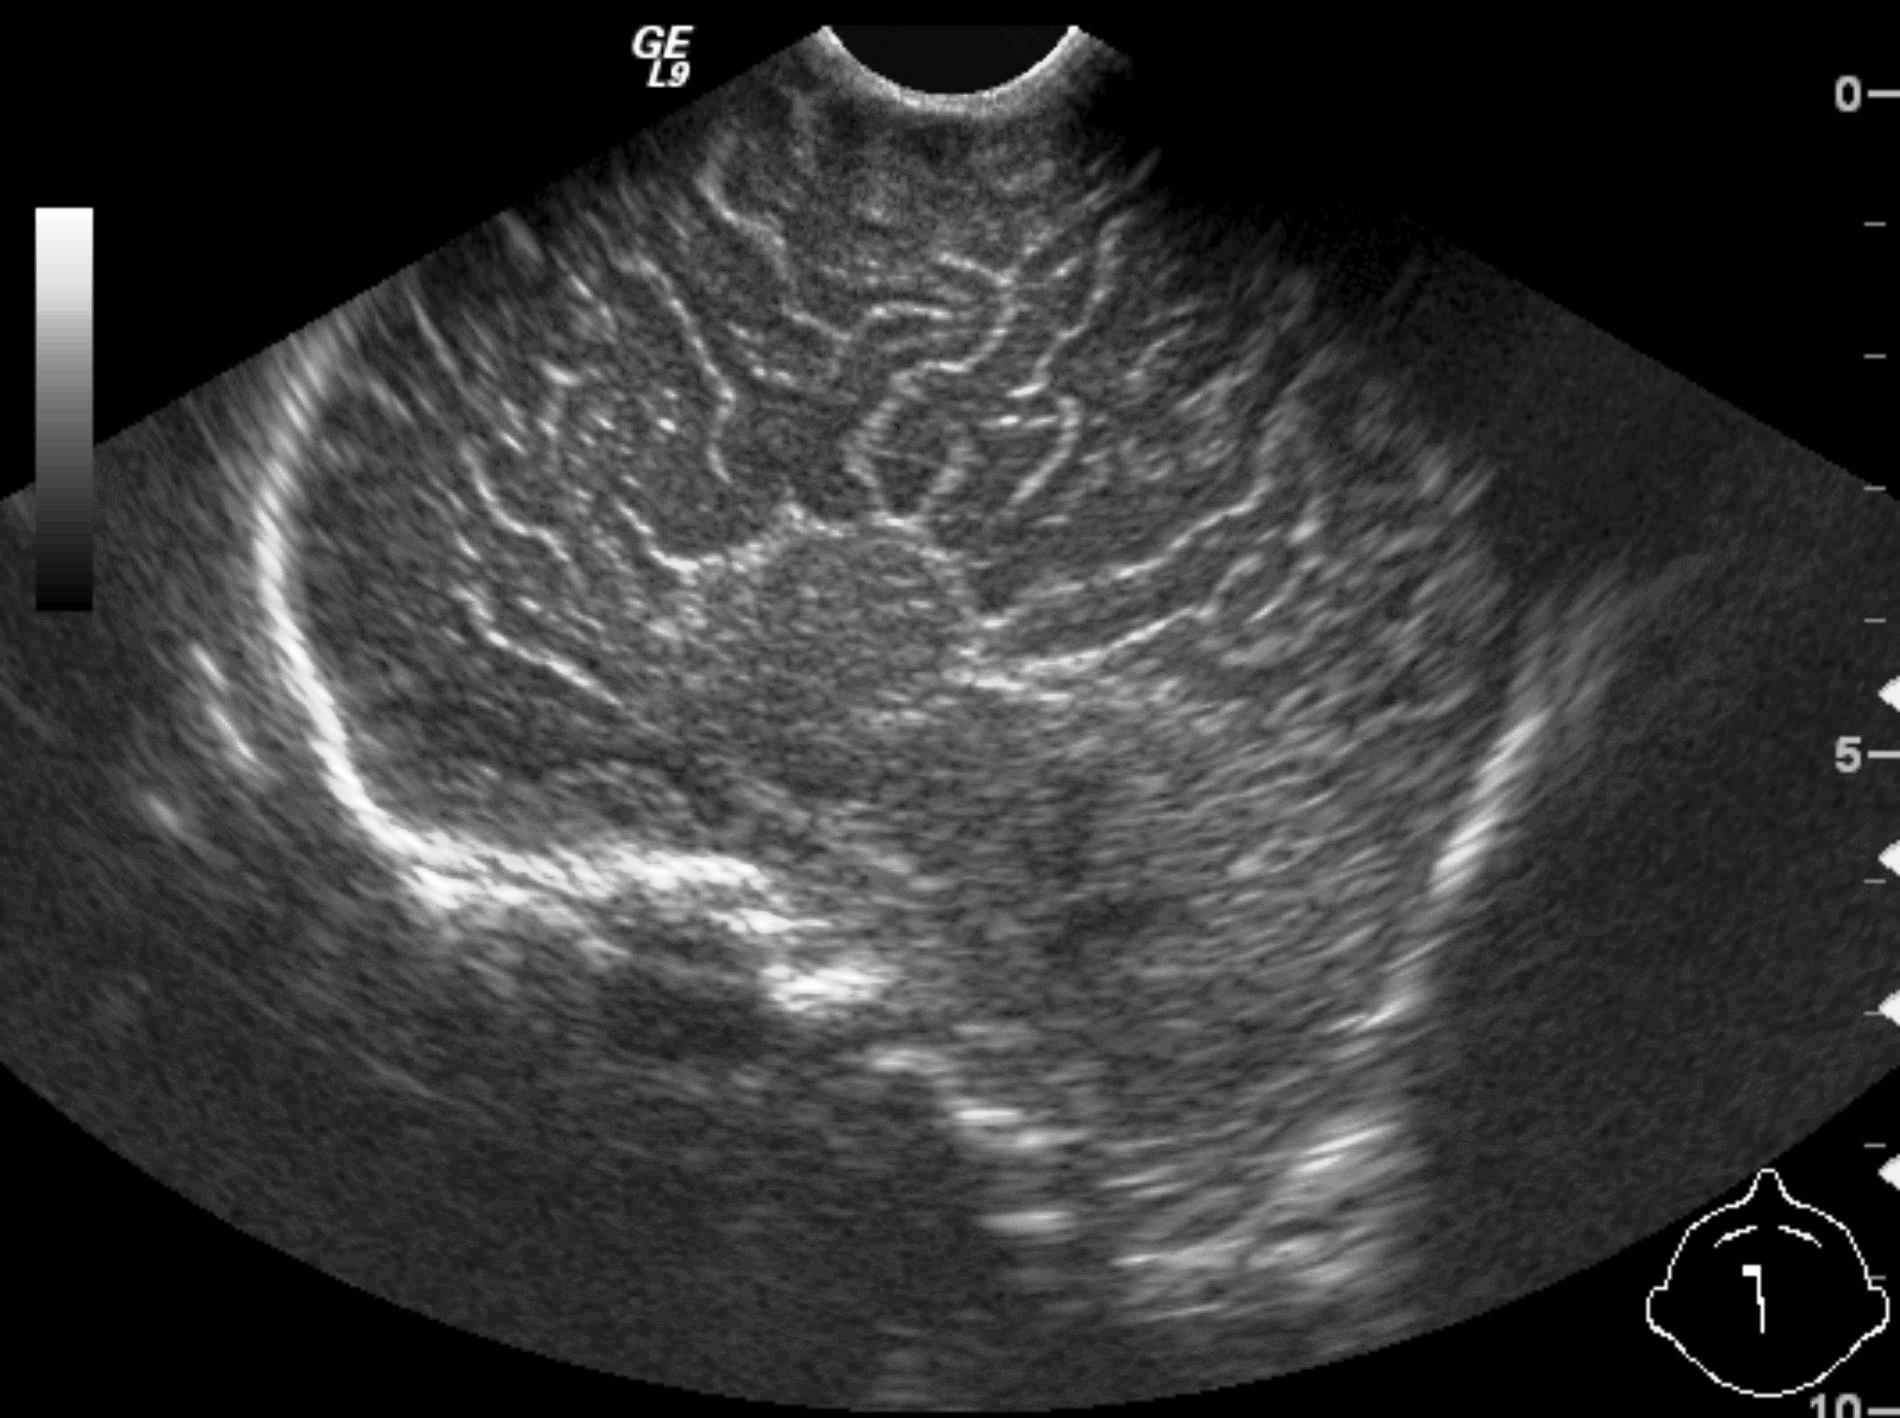

Invagination. A distal intestinal loop invaginating to a proximal intestinal loop can result in a mechanical intestinal obstruction, and cause ischemic damage. It most frequently occurs in infants (3-24 months) with recurring, colic-like complaints, distended intestines, a palpable mass and with frequent vomiting and bloody stool. Invagination requires immediate diagnosis and desinvagination. US exam reveals the invaginated intestines as a “target” sign in axial cross section and looks like a “pseudokidney” in longitudinal cross section. The therapy is hydrostatic or pneumatic desinvagination. Perforation and/or peritonitis are absolute contraindications to these procedures. Hydrostatic desinvagination can be performed under fluoroscopy or with US guidance and is considered successful if air or the contrast material appears in the terminal ileum and the invaginated loop disappears. If these efforts do not succeed, surgical desinvagination is needed.